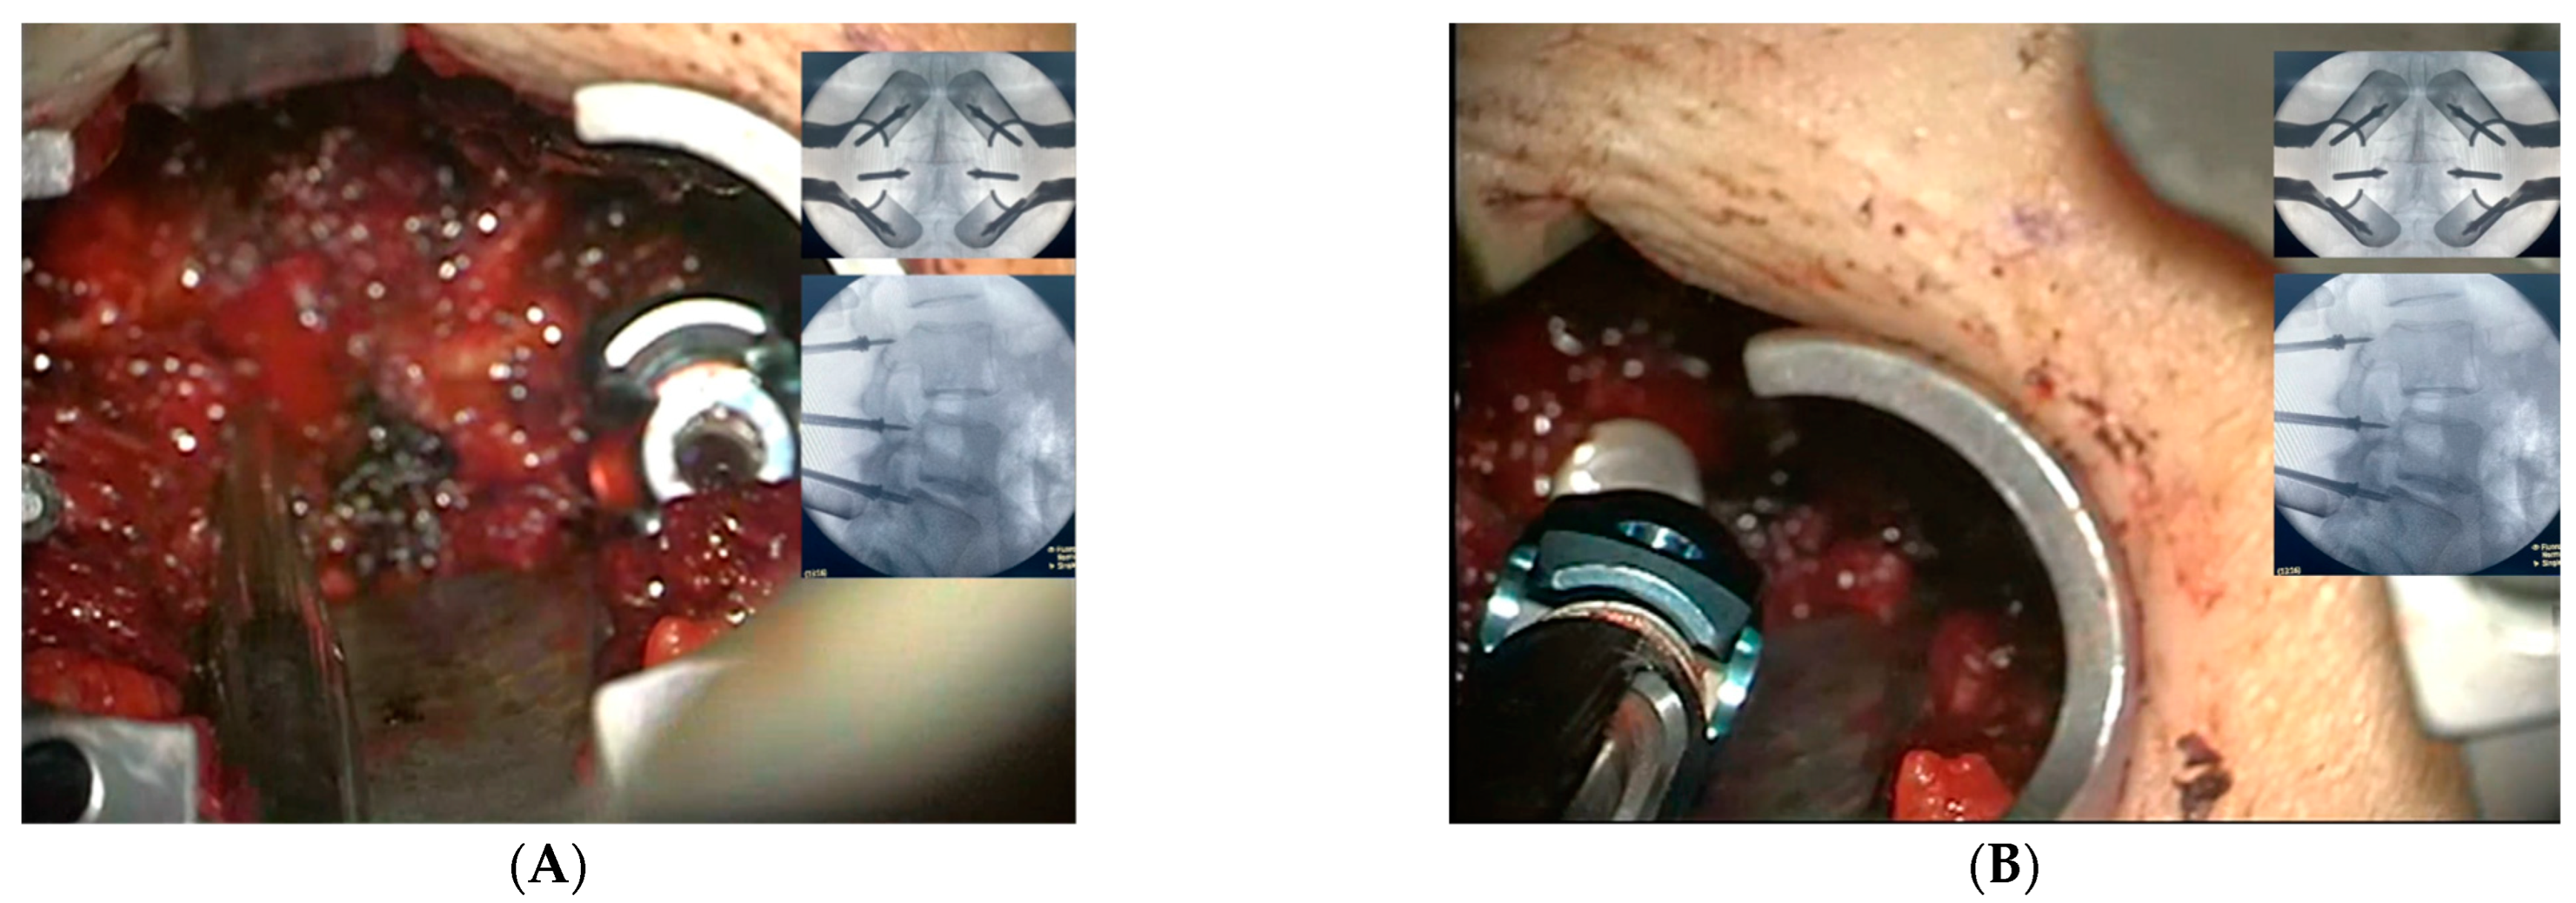

2.3. Surgical Intervention and Marker Screw Utilization